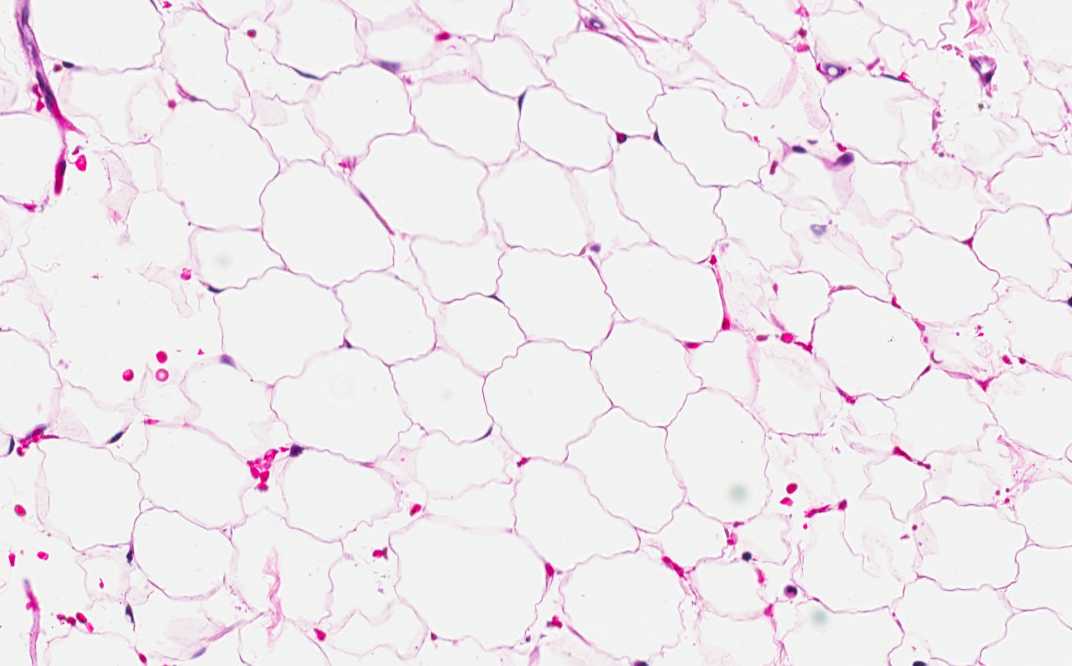

Area 3: Compare area 2 to the periadrenal adipose tissue, there is no myeloid cells in the peradrenal adipose tissue.